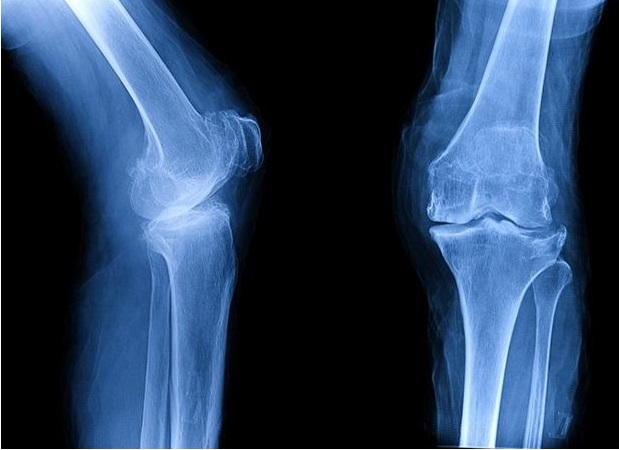

Με τον γενικό όρο αρθρίτιδα περιγράφεται μια φλεγμονώδης πάθηση των αρθρώσεων που χαρακτηρίζεται από καταστροφή των στοιχείων της άρθρωσης, των μηνίσκων, του υποχόνδριου οστού και κυρίως του αρθρικού χόνδρου. Οι πιο κοινές μορφές αρθρίτιδας είναι η οστεοαρθρίτιδα, η ρευματοειδής και η μετατραυματική αρθρίτιδα. Το γόνατο είναι από τις συχνότερα προσβαλλόμενες αρθρώσεις.

Οι ασθενείς διαμαρτύρονται κυρίως για πόνο, ο οποίος περιγράφεται έως και αφόρητος, και ο οποίος τις νυχτερινές ώρες εμποδίζει την ανάπαυσή τους κατά τον ύπνο, και για σημαντικό περιορισμό της καθημερινότητάς τους με αδυναμία εκτέλεσης βασικών κινήσεων, δυσκολία στην έγερση από την καθιστή θέση και μείωση της απόστασης βάδισης.

Η απόφαση για την αντικατάσταση του γόνατος λαμβάνεται συνυπολογίζοντας τον τρόπο ζωής του ασθενή, τα προσδοκόμενα οφέλη και τους κινδύνους της επέμβασης. Οι παράγοντες που επιβάλλουν την χειρουργική αντιμετώπιση αφού πρωταρχικά επιβεβαιωθεί ακτινογραφικά η ύπαρξη αρθρίτιδας, είναι η επηρεασμένη καθημερινή λειτουργικότητα και ο έντονος πόνος. Δεν υπάρχει κατάλληλη ηλικία για την αρθροπλαστική. Εάν ο ασθενής δεν μπορεί να υπομένει άλλο τον πόνο και την επηρεασμένη ποιότητας ζωής του και επιθυμεί να είναι δραστήριος η επέμβαση δύναται να πραγματοποιηθεί ανεξαρτήτου ηλικίας, αρκεί να το επιτρέπει η συνολική κατάσταση της υγείας του. Συνήθως βέβαια, οι υποψήφιοι για την επέμβαση είναι μεγαλύτεροι σε ηλικία καθώς η αρθρίτιδα είναι συχνότερη μετά τα 60 έτη.